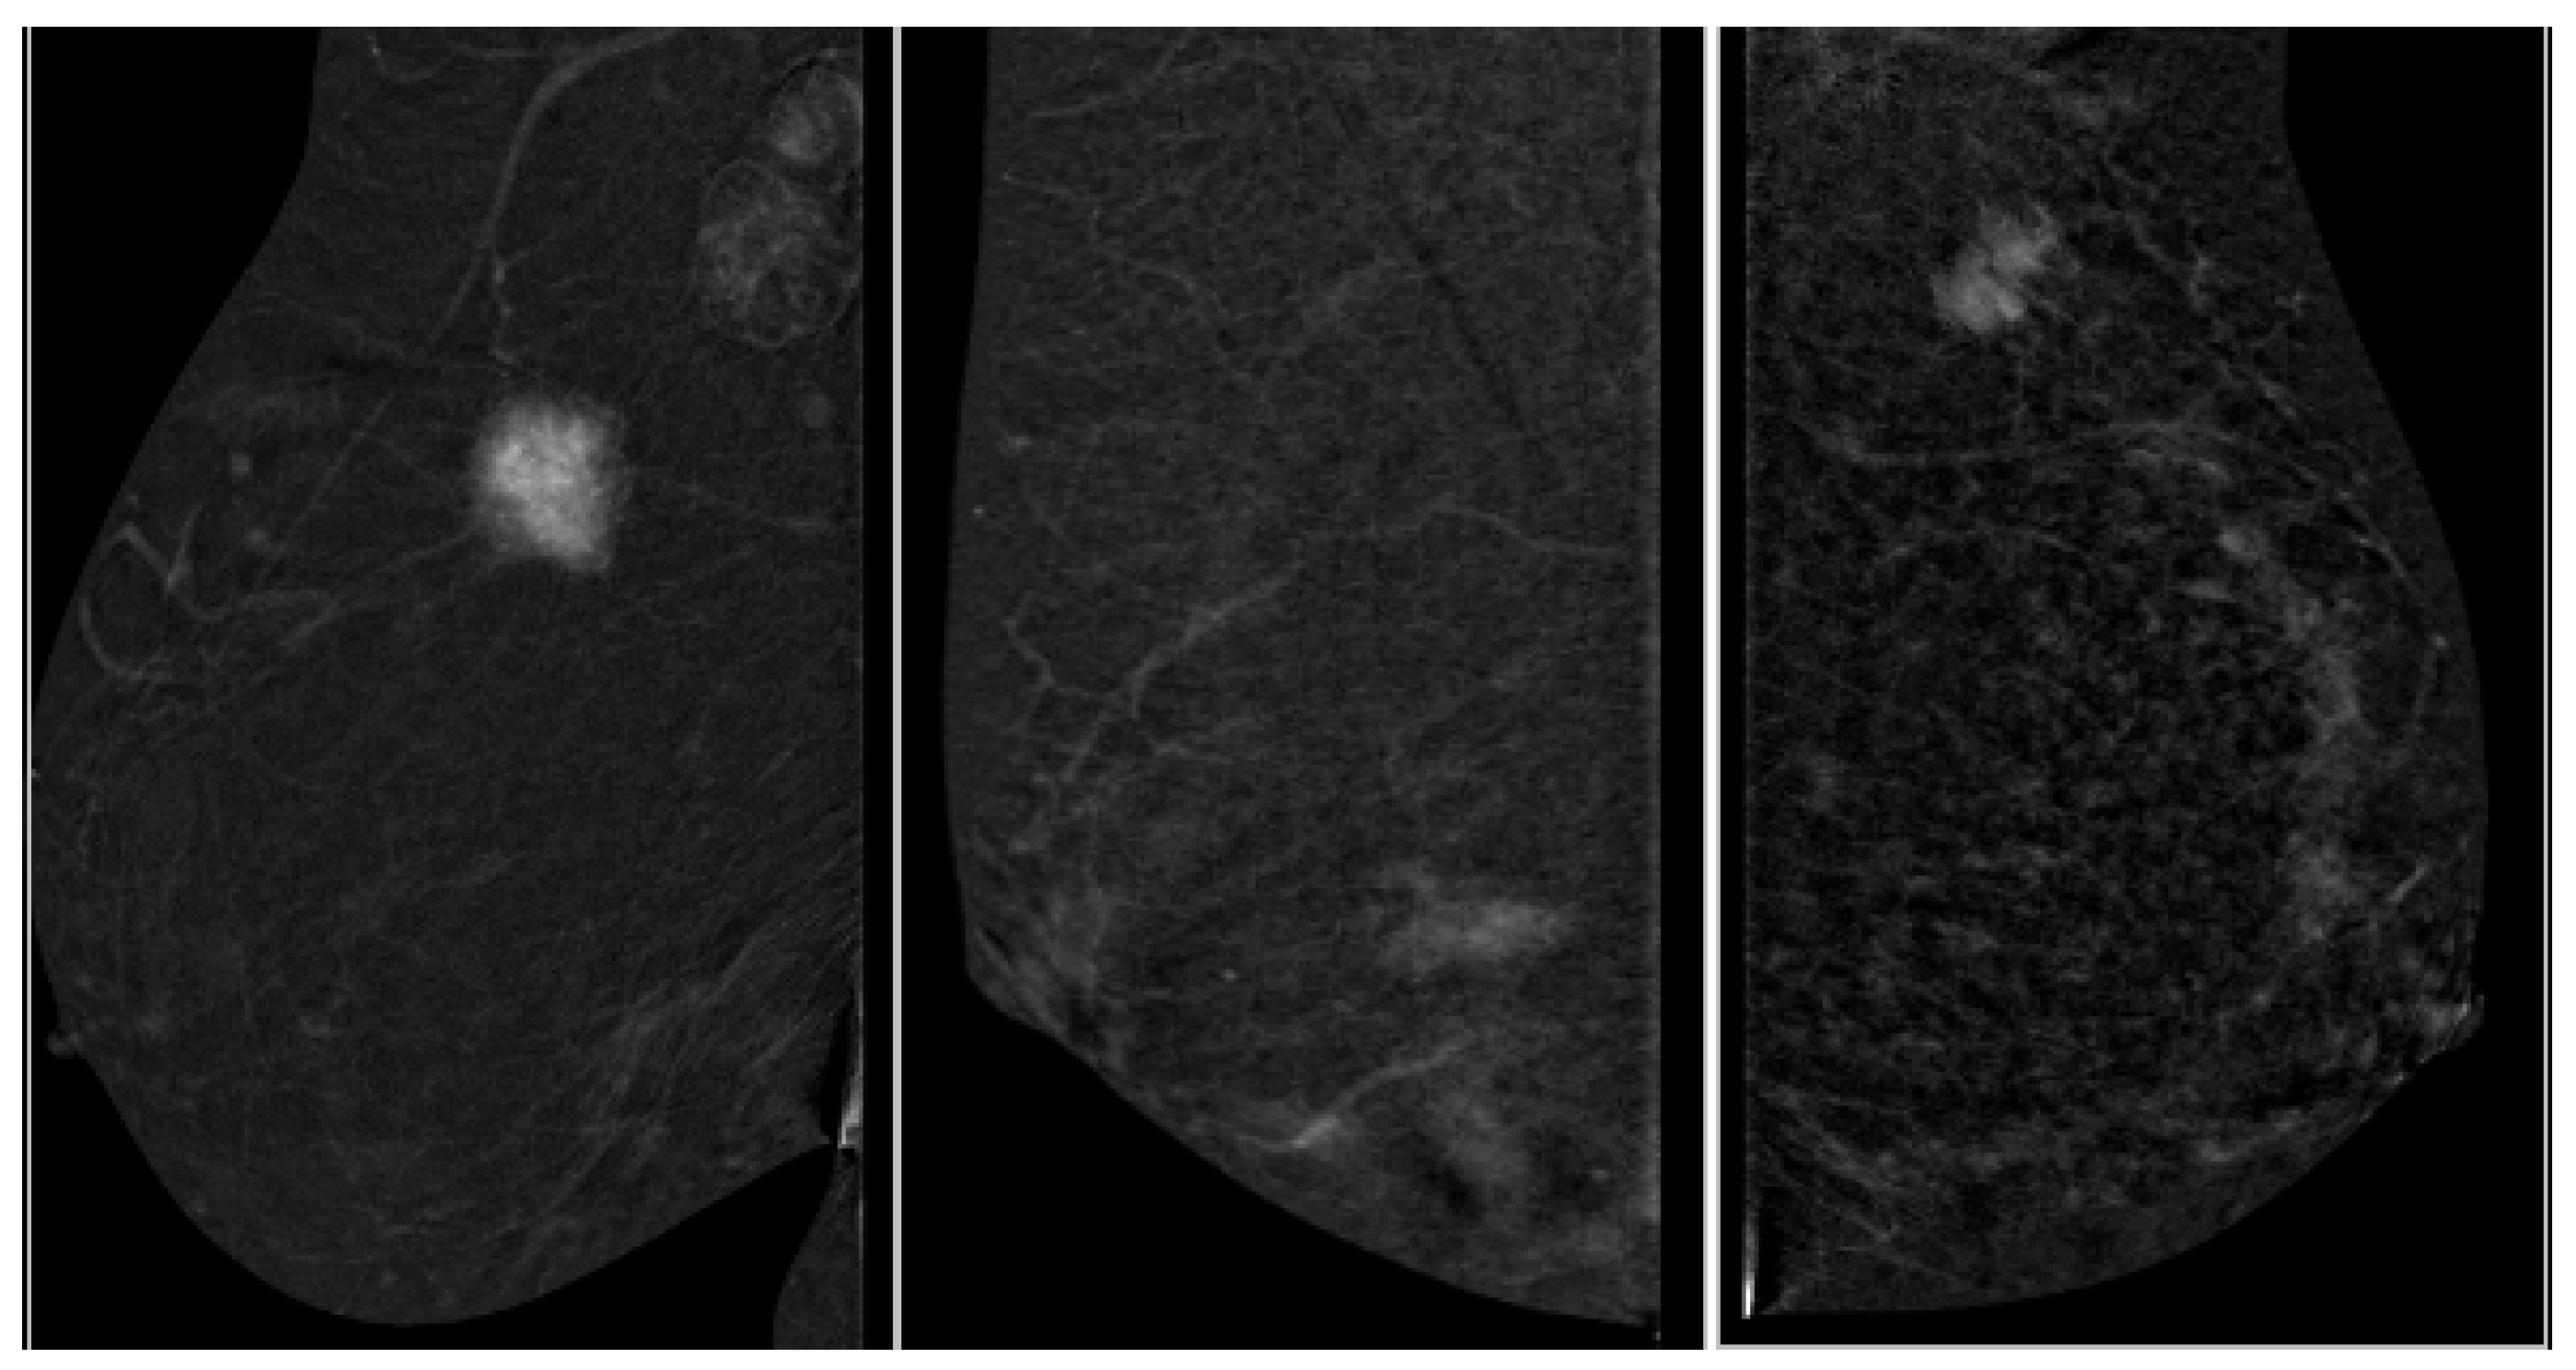

3.3. Correlation of Ki-67 and Enhancement Intensity

3.4. Correlation of Contrast Homogeneity and Tumor Grade